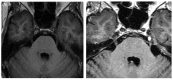

Intracranial trigeminal schwannomas are rare tumors. Patients usually present with symptoms of trigeminal nerve dysfunction, the most common symptom being facial pain. MRI is the imaging modality of choice and is usually diagnostic in the appropriate clinical setting. The thin T2-weighted CISS 3D axial sequence is important for proper assessment of the cisternal segment of the nerve. They are usually hypointense on T1, hyperintense on T2 with avid enhancement post gadolinium. CT scan is supplementary to MRI, particularly for tumors located in the skull base. Imaging plays a role in diagnosis and surgical planning. In this pictorial essay, we retrospectively reviewed imaging findings in nine patients with pathologically proven trigeminal schwannoma. Familiarity with the imaging findings of intracranial trigeminal schwannoma may help to diagnose this entity.